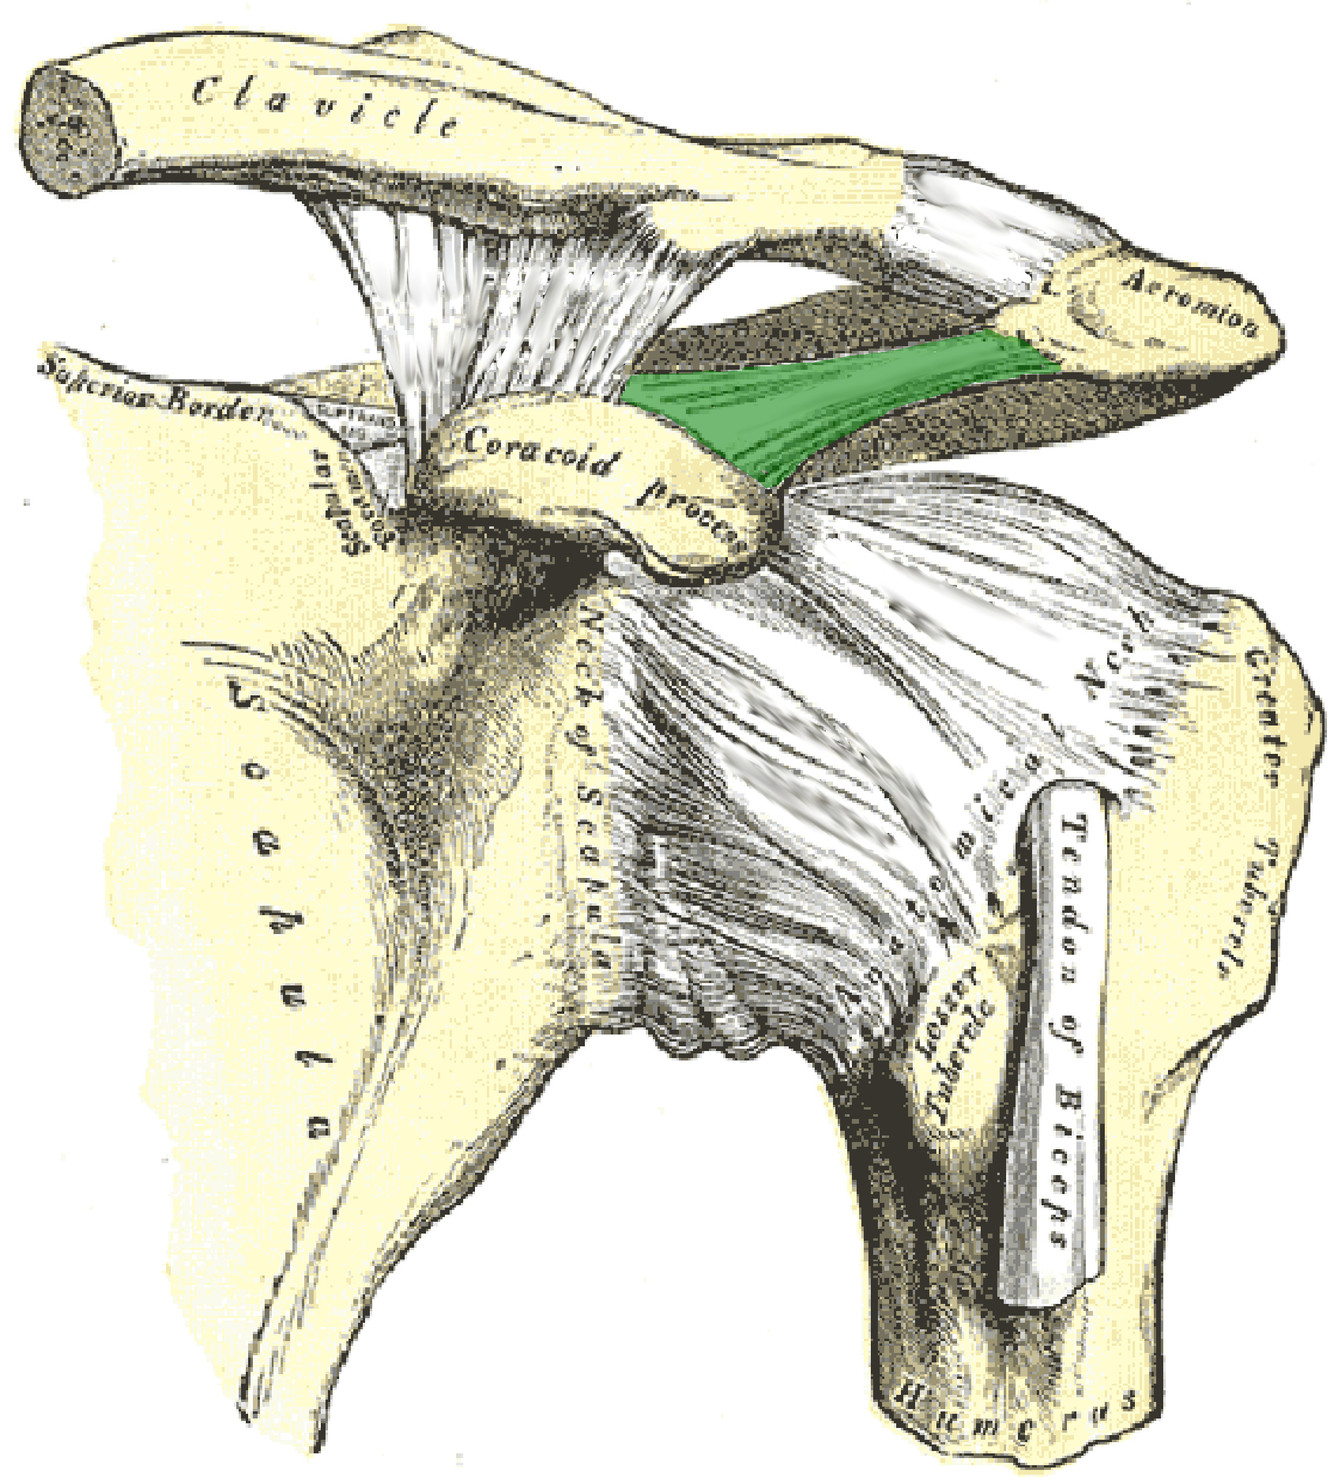

What is this structure?

Coracoacromial ligament of shoulder